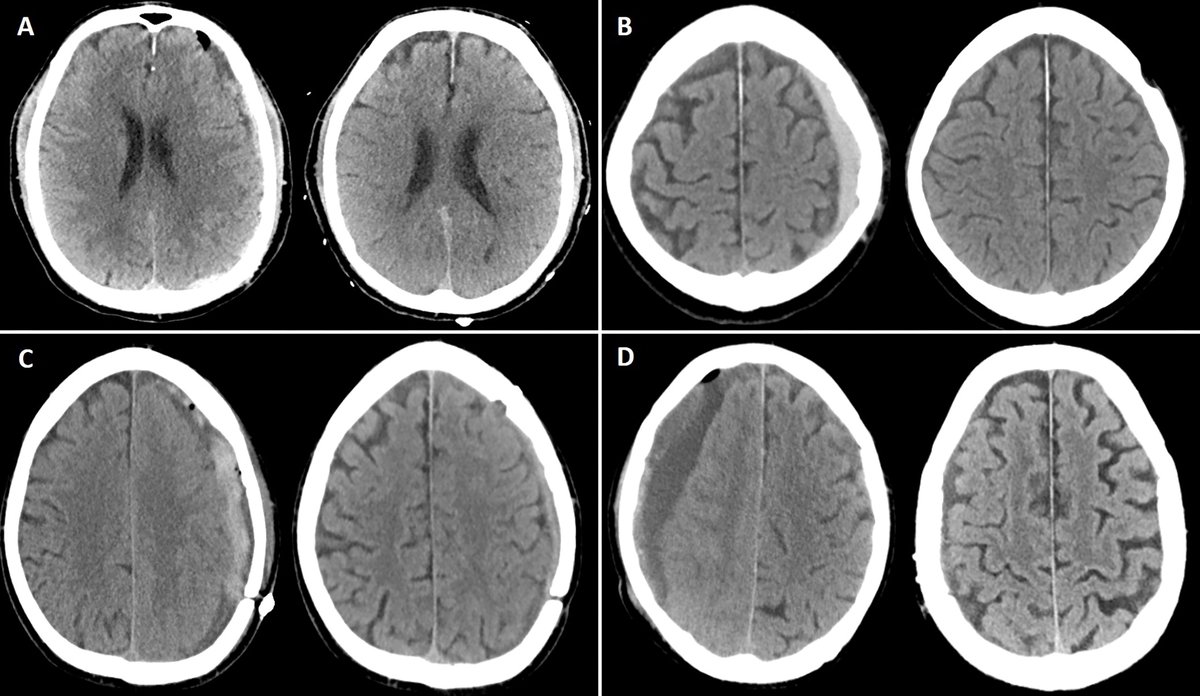

Great talk by @ShahidNimjee about VWF inhibiting aptamer for thrombolysis. This research has come along way and will improve stroke therapy in the future. It may be the beginning of the end of stroke mechanical thrombectomy. #SNIS2023 @OSUWexMed @NeurosurgeryOSU